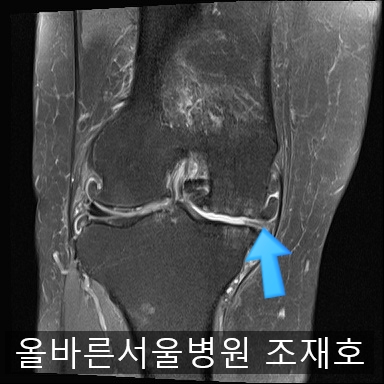

为了掌握具体情况拍了MRI。

内侧关节软骨几乎不见,软骨板也受损严重。软骨损伤部位充满关节液。

虽然前方十字韧带粘液样变性,但稳定性无异常

后方十字韧带无明显异常。